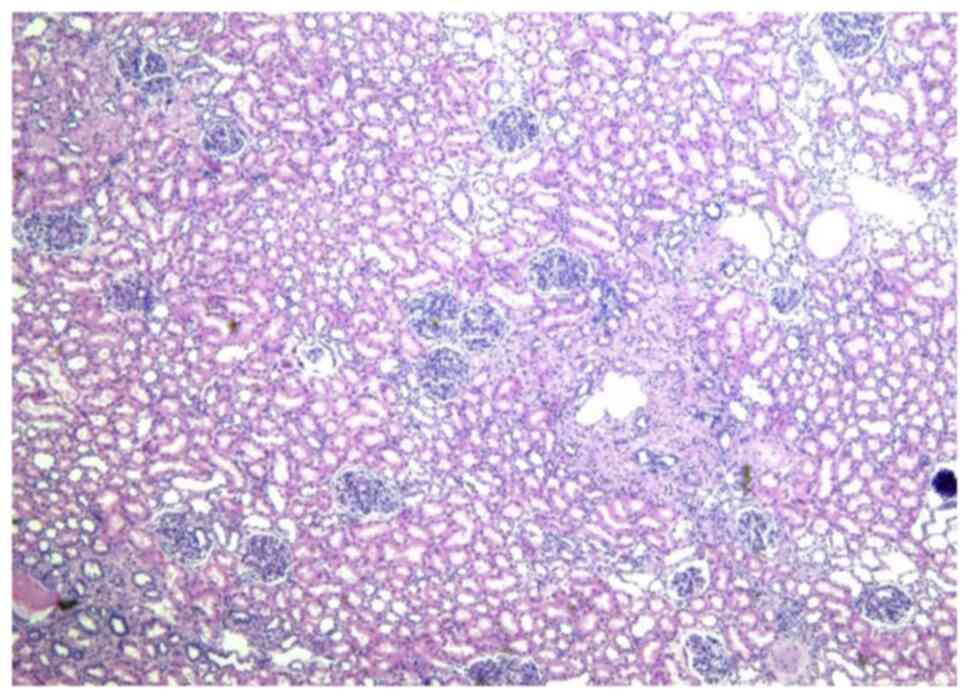

The 20-year-old young female patient has been diagnosed with epilepsy since childhood and has been treated with valproate sustained release tablets. She was admitted to the department of neurology of our hospital due to repeated daze, occasionally accompanied by nausea, vomiting, and hallucinations. Physical examination showed that the patient was slightly slow in response and expression, and her calculation was poor. Multiple small papules and nodules can be seen on her cheeks. Palpation of the right upper abdomen revealed a tough mass with smooth surface, fixed position, and no tenderness. Valproic acid test in the laboratory showed that the patient's CYP2C9 genotype was CYP2C811, and the enzyme activity was fast metabolism (EM) type. POLG (A467TG>A) was of wild homozygous type, POLG (W748SC>G) wild homozygous type SLCO1B1 genotype was 1b1b, and ApoE genotype was E2E4. The electrolyte, liver enzymes, renal functions, cardiac functions, routine examination of blood and urine, and coagulation functions were normal. Abdominal enhanced CT scan showed that the liver was obviously pushed, and the spine was scoliotic. A huge mass occupied the right upper quadrant, with a size of ~236x125x149 mm. The CT value was about-78HU. Blood vessels could be seen inside, and the boundary between the blood vessel and the kidney was unclear. The surrounding tissue was pushed, and the right kidney was displaced to the middle abdomen (Fig. 1). Moreover, two inhomogeneous enhancement nodules were present in the middle and lower pole of the right kidney. The larger nodule (26x33 mm in size) was in the right kidney. Multiple low-density shadows with no enhancement were also evident in the right kidney. In the left kidney, an inhomogeneous enhancement nodule was present on the upper pole, and its size was 28x29 mm. Multiple no enhancement low-density shadows (Fig. 2) were distributed in the left kidney. The right adrenal gland was unclear. The shape, size, and density of the left adrenal gland were normal. No obvious dilation and hydrops were observed in the bilateral renal pelvis and calyces, and the intestinal curve was pushed. No obvious enlarged lymph nodes and no ascites signs were seen behind the peritoneum. The result of the Chest CT scan showed multiple nodular shadows with sizes of ~2-3 mm in the right upper lobe and dorsal right lower lobe. A nodular shadow, ~3 mm in size, was seen under the pleura of the tongue of the left upper lobe. Cranial MRI showed the following results. Abnormal signals were detected from the bilateral cerebral hemisphere cortex, right putamen, and right caudate nucleus. A slightly low signal was observed in T1WI. A slightly high signal was observed in T2WI and FRAIR. The DWI showed no diffusion with limited high signal. Under the bilateral maxillary sinus mucosa, round-like long T1 long T2 signal shadows were seen, and the larger one was ~15x17 mm in size. Considering the patient's medical history and the results of laboratory examination, the diagnosis included epilepsy, giant hamartoma of the right kidney, hamartoma of the left kidney, multiple pulmonary nodules, and abnormal head signals, which were highly consistent with the manifestations of TSC. Although the patient had no obvious symptoms of abdominal visceral compression, and laboratory examination showed no obvious abnormalities in the kidney function. The compression of a huge abdominal mass caused the liver and kidney to deviate significantly and led to spine scoliosis. The continued growth of the mass may affect the function of the kidney and the digestive system. Moreover, the overgrown mass puts the patient at risk of spontaneous rupture and bleeding, which are life-threatening. So, the mass was indicated for surgical resection. After comprehensive preparation before the operation, the patient underwent open mass resection and right kidney partial resection. The appearance of the tumor is shown below (Fig. 3). Postoperative pathological results (Fig. 4) confirmed RAML, and the immunohistochemical results were as follows: HMB45 +, SMA +, Des +, S100 +, and Ki67 (1% +) (Fig. 5). The patient recovered smoothly after the operation. No recurrence of kidney tumors was found. Nodules in the lungs and abnormal head signals remained the same after the half-year follow-up period.

Figure 4

H&E staining of tumor tissue (magnification, x100). A high quantity of vascular tissue, with scattered fat cells and smooth muscle is present. H&E, hematoxylin and eosin.